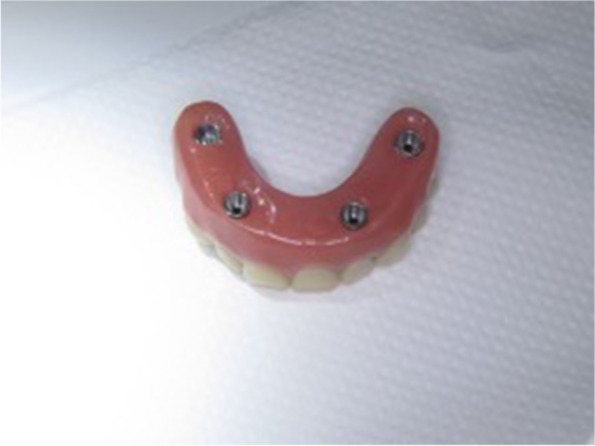

Fig. 8.

The provisional acrylic prosthesis